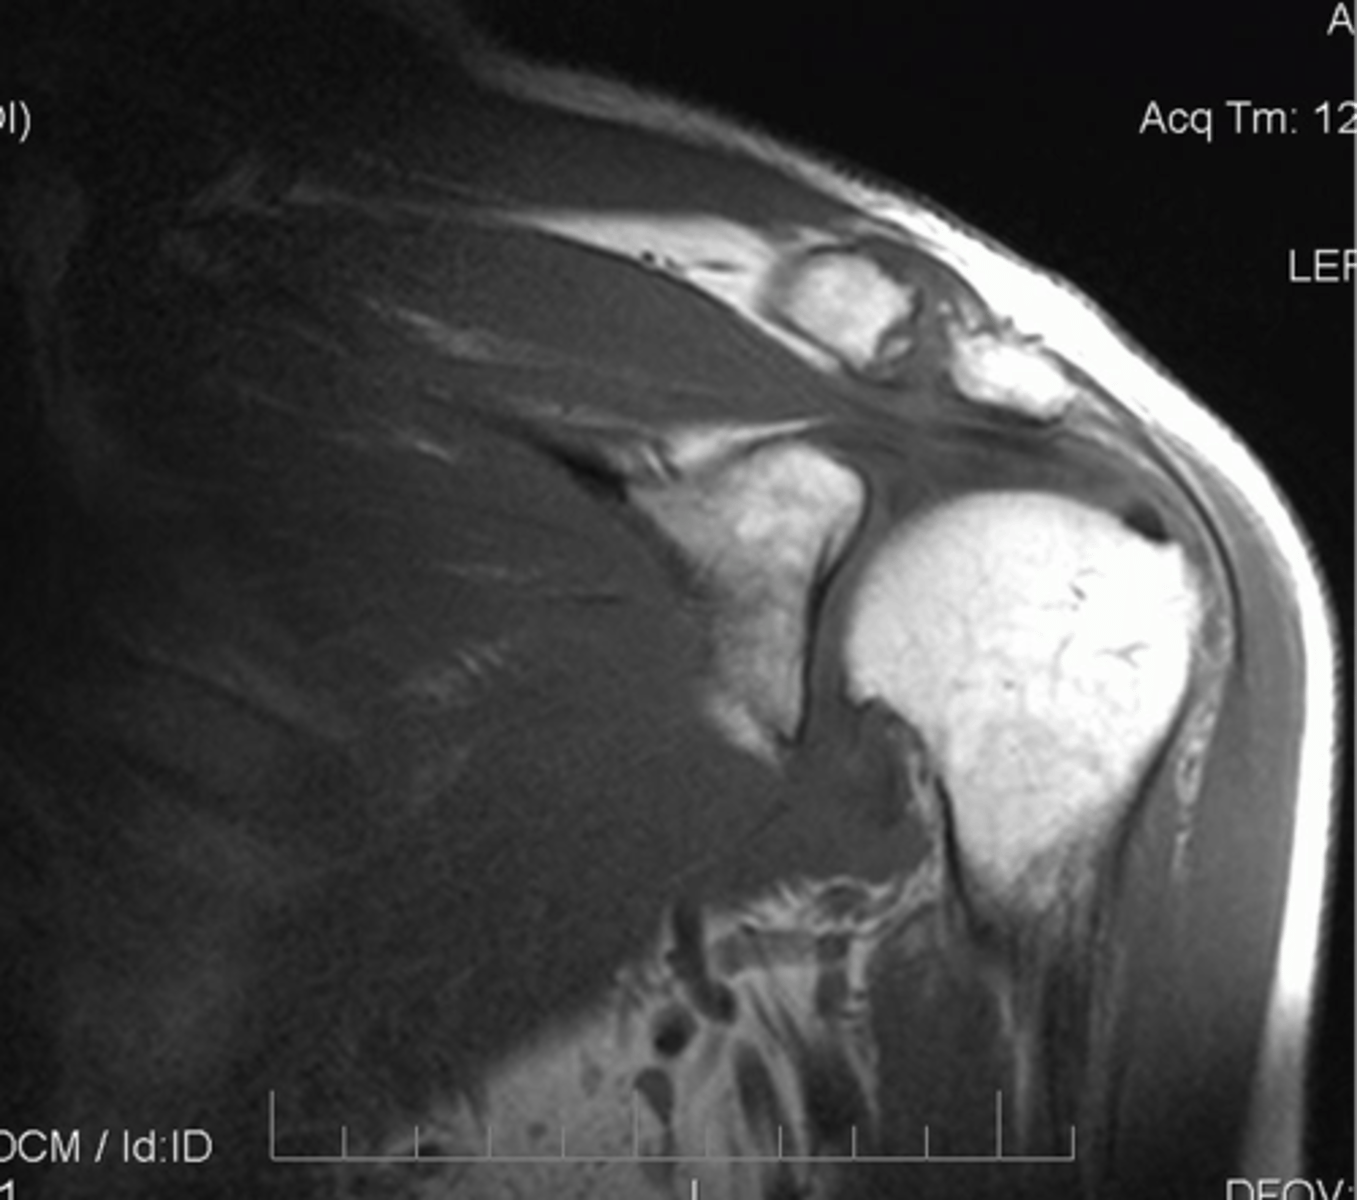

Full-thickness tear!!

- fluid (area of tear) in white

- retraction in red

- bucking in green

What is this image depicting w/ the rotator cuff? (hint: it is a T2 image)

Complete thickness tear of the supraspinatus w/ major bucking and retraction as the muscle pulls the tendon back

What are these images depicting w/ the rotator cuff?